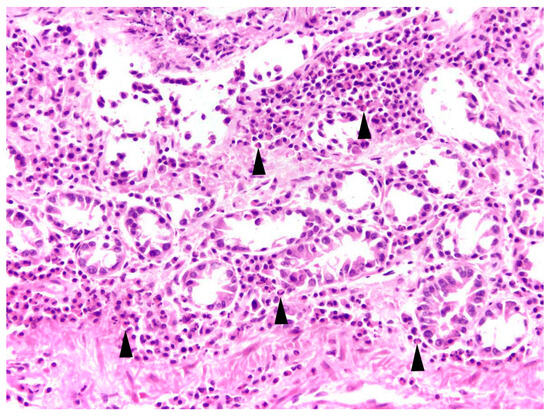

The main type of hepatitis was non-purulent with different proportions of lymphocytes, plasma cells, and macrophages (93.0%, n = 80; Figure 4), followed by purulent (14.0%, n = 12), necrotising (5.8%, n = 5), and granulomatous type (5.8%, n = 5). Eight cases (9.3%) of hepatitis showed a mixed inflammatory type.

Intestine: The most common finding in histopathological analyses, which was observed in 99 out of 155 investigated hares (63.9%), was the detection of parasites or parasite stages in the intestine. Mainly different stages of protozoal organisms were found (74.7%, n = 74) and either detected in the intestinal epithelium (n = 35, Figure 5) or in the intestinal lumen (n = 19).

In 81.0% of cases, the enteritis was non-purulent (n = 17) with various infiltrations of lymphocytes, plasma cells, histiocytes, and partly eosinophils (Figure 8), and in 33.3%, a granulomatous (n = 7) inflammatory type was present. A mixed inflammatory type was detected in 14.3% (n = 3) of affected animals.

All inflammations of the kidneys were non-purulent, with interstitial infiltrations of lymphocytes, macrophages, and plasma cells (Figure 12). In one adult male, fibrosis and depression on the kidney surface were observed.